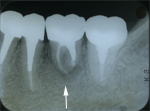

1.移植前(1985年)

第一大臼歯(矢印)がひどい虫歯で、歯肉が、歯の中に入り込んでいます。 |

2.移植前(X線写真)

第一大臼歯(赤矢印)は保存不可能で抜歯。

その後に、横向きに埋もれている親知らず(白矢印)を移植することにしました。 |